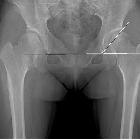

of hip impingement syndrome in patients with multiple hereditary exostoses. Plain radiographic measurements to evaluate the hip joint deformities. a The femoral neck-shaft angle is determined by measuring the angle created by a line in the central axis of femoral shaft and a second line created by the connection of the femoral head center to the mid portion of the femoral head and neck junction contour. b Sharp’s angle is determined by measuring the angle created by a line connecting the acetabular tear drops and a second line connecting a tear drop and the sourcil end. c The center-edge angle is determined by measuring the angle created by a line connecting the vertical line to the tear drop line through the center of the femoral head and a second line from the center of the hip to the lateral acetabular wall margin

Characteristics